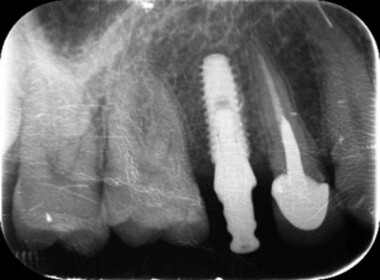

| 0709 #36#37 左下第一第二大臼齒 |

![]() |